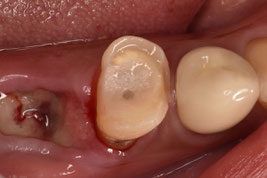

2日目にファイバーコアを植立しました。

軸面の健全歯質を大幅に残したうえで、オーバーレイの形態で修復しました。インジェクションモールディング法を応用しております。直接修復なので、海外からの来院であっても、短期滞在で対応可能です。

1回法による根管治療で進めました。1回法だと3時間くらい口を開けっ放しになるので、患者さんは辛いと思います。ご協力いただき大変恐縮です。

ダイレクト修復に完全移行してから、歯冠形成が大きく変わりました。アンダーカットを積極的に付与するようになり、形成のキレイさを気にせず、健全歯を最大限残す形態になりました。

コア部分にグラスファイバー繊維を含有したエバーXフロー(GC)を用いております。エバーXフロー(GC)を使用するようになってから、修復物の破損が圧倒的に少ない!特にダイレクトブリッジの破折が目を見張るほどに減少しました!技術の向上に感謝です。

インジェクションモールディング法を用いて、ダイレクトクラウンにて完了させました。ファイバーコアによる支台築造と同時にダイレクトクラウンを成形するため、歯根・築造体・クラウンとが一体化したモノブロック構造で強度を担保できます。ファイバーコアからダイレクトクラウンまで一気に進めて、だいたい2時間の施術時間です。施術中にドクターが離れることができないのですが、圧倒的な時間短縮です。